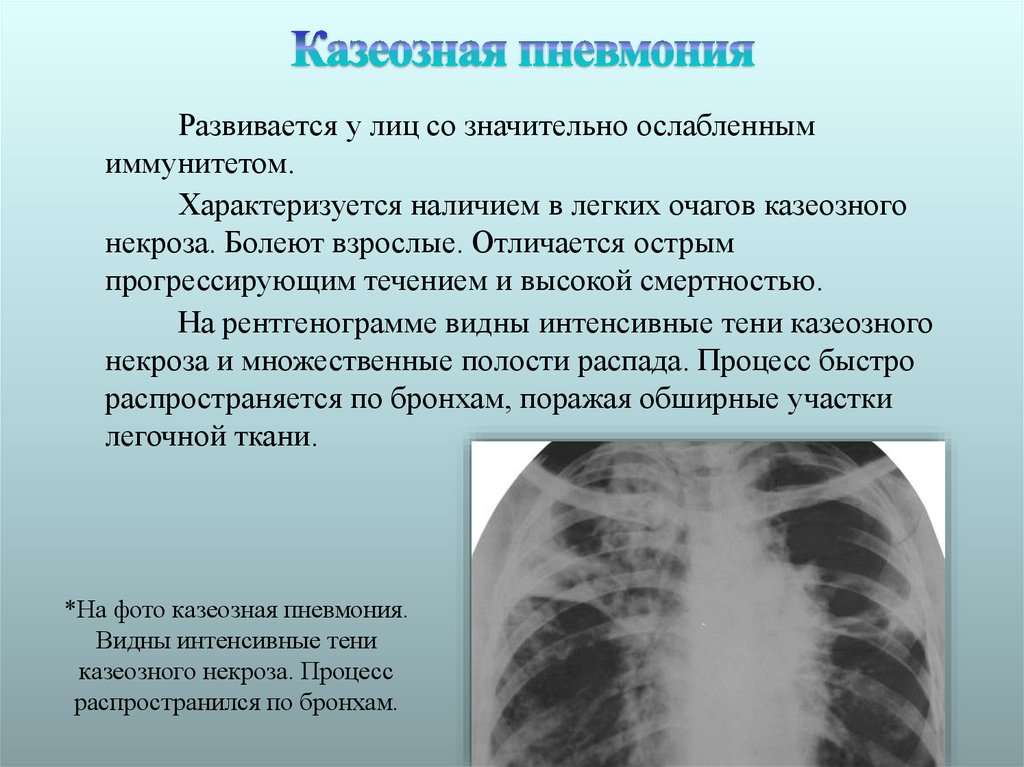

Очаговый и инфильтративный туберкулез презентация - 94 фото